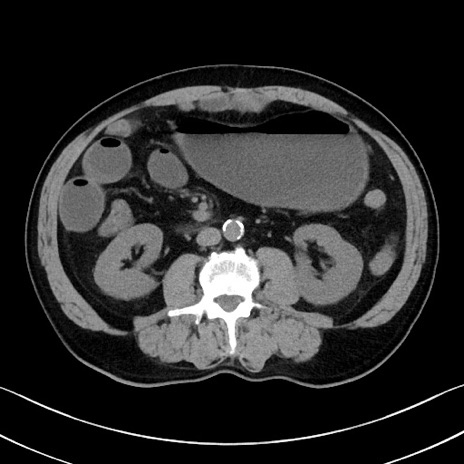

症例35(横断像)

【症例】70歳代 男性

【主訴】腹部膨満、嘔吐

【現病歴】昨日より腹部膨満感出現。本日増悪し、仙痛出現。嘔吐あり、受診。

【既往歴】糖尿病、胆摘後

【身体所見】BP 149/80mmHg、HR 74/min、BT 35.9℃、腹部:膨満、軟、圧痛なし。腸雑音減弱あり。上腹部正中切開瘢痕あり。

【データ】WBC 13500、CRP 1.72